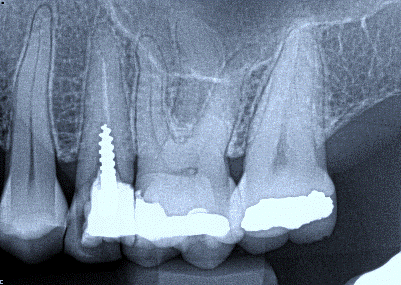

2. (Select ONE OR MORE correct answers)

What observation(s) can be made for tooth 4.7?